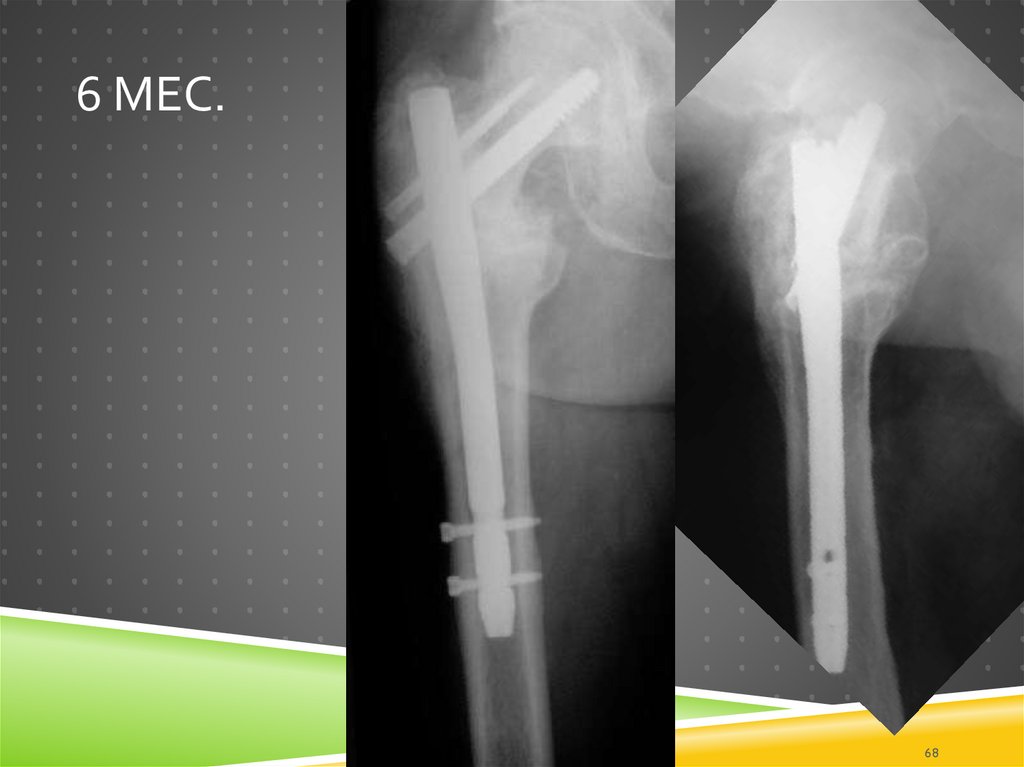

68. 6 мес.

6 МЕС.

68